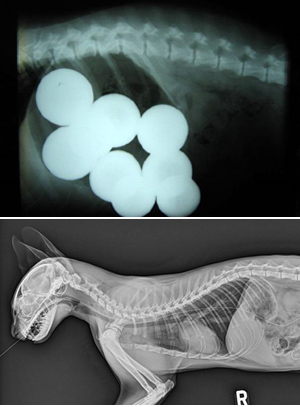

이번 대회의 영예(?)의 우승은 무려 당구공 9개를 삼킨 하운드 종의 개가 차지했다. 오리건주 베이쇼어 동물병원에서 치료받은 이 개는 자신의 위 안에 당구공 9개를 가지런히(?) 모아두어 우승을 차지했다.

이중 눈길을 끈 사진은 기타줄을 그대로 삼킨 고양이. 이 고양이의 X-레이 사진을 보면 몸 전체에 기타줄이 펼쳐져 있다. 이밖에도 주인의 틀니를 삼킨 개, 접착제를 통째로 삼킨 개도 눈길을 끌었다.